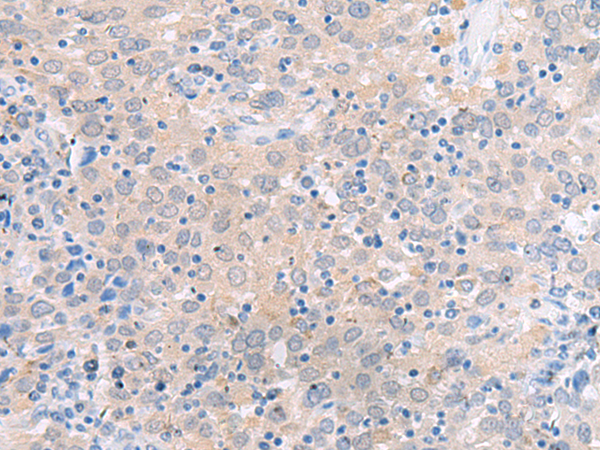

分类: 科研抗体货号: P11280别名: 24p3, MSFI, NGAL应用: WB,IHC反应种属: Human